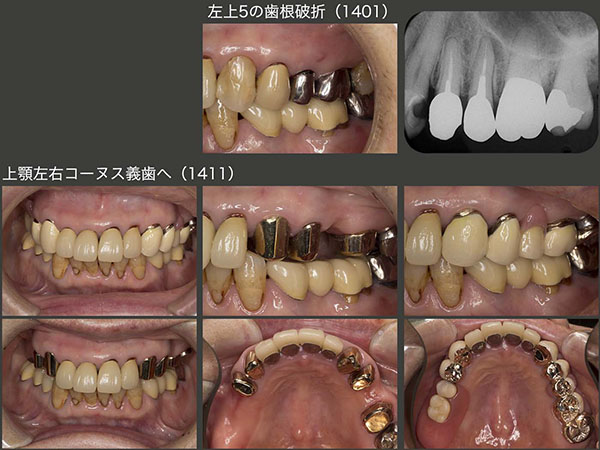

治療終了7ヵ月後の2014年1月,恐れていた歯根破折が左上5に生じた.このことは,右上に義歯を装着するときに,耳にたこができるぐらい説明してきたので,すんなり左上の治療を受け入れてくれた.11月に,上顎左側にも可撤式ブリッジ(コーヌス義歯)を装着した.

2015年5月,これも恐れていたと言うより予想どおりであるが,右上に問題が生じた.強いて言えば,もう少し年を重ねた先に起こるのでは?また,右上4が先に歯根破折すると思っていた.ところが実際は右上3に歯根破折が生じた.幸い破折線が根尖まで達していなかったので再植することができた.しかし,右上3は支台歯として力,特に水平力を担うには,歯根が短く無理があるため,残りの前歯4本を支台歯として組み込み,上顎の支台歯全てを2次固定し,全体で力に対抗できるようにした.